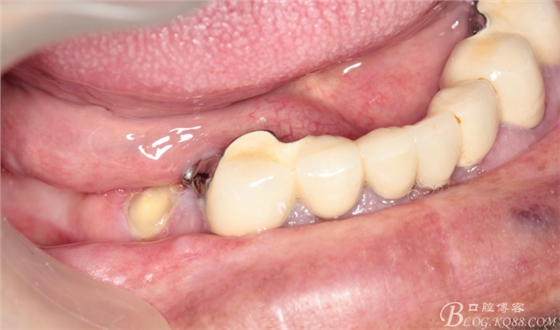

修復(fù)兩年后患者復(fù)診

44作為覆蓋基牙保留完好,牙周狀態(tài)良好,附著體基牙有一定的牙齦萎縮,

上頜套筒冠基牙無松動(dòng),對(duì)比做牙前得到較大改善